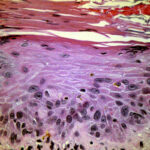

In the atrophic type of actinic keratosis, hyperkeratosis usually is slight. The epidermis is thinned and devoid of rete ridges. Atypicality of the cells is found predominantly in the basal cell layer, which consists of cells with large hyperchromatic nuclei that lie close together. The atypical basal layer may proliferate into the dermis as buds and ductlike structures. It may also surround as cell mantles the upper portion of pilosebaceous follicles and sweat ducts, the epithelium of which otherwise appears normal . |